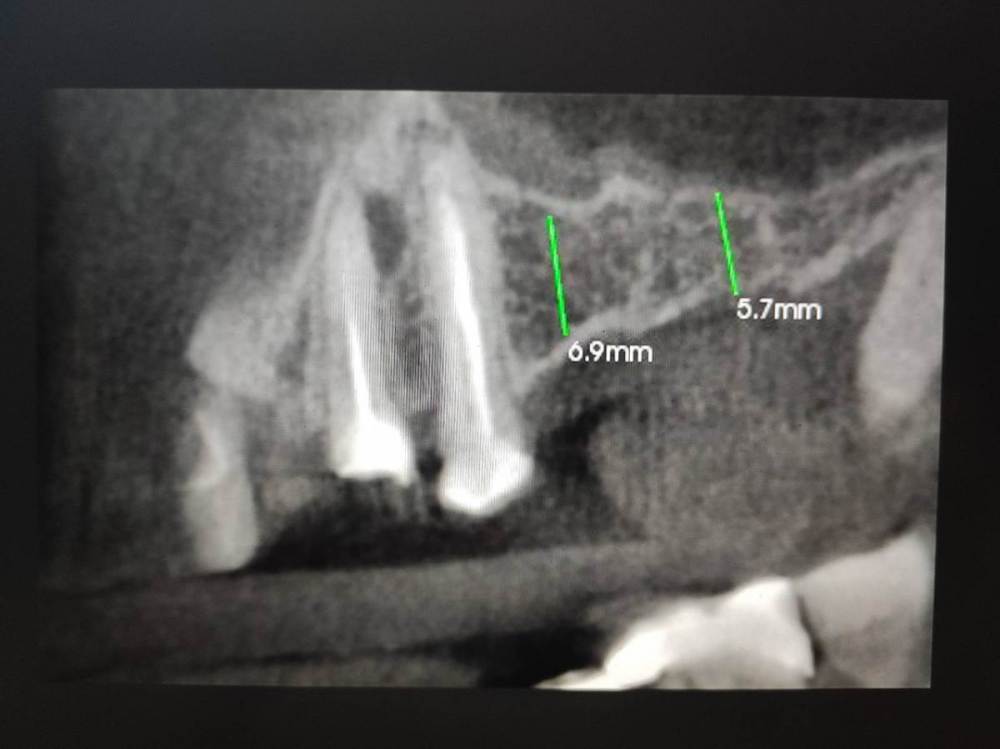

ЕвгенийПет Опубликовано 30 ноября, 2023 Поделиться Опубликовано 30 ноября, 2023 (изменено) Доброго дня! Уважаемые врачи, проблема и вопросы у меня в следующем: Примерно в 2010 году пришлось удалить 26 и 27 зубы (сначала свищ на одном, а со временем (около года) уже не помню почему и второй. С тех пор жую только на правую сторону, а сейчас под удаление 15 (снимок №1 во вложении), весной отекло лицо, обнаружили гранулему и вскрывали абсцесс. Тоже вопрос, хотя даже я по снимку вижу, что его не спасти, но а вдруг? Так вот, с жеванием теперь возникнут явные проблемы (отсутствует 46 зуб), и нужно срочно что-то решить со вторым рядом. Сразу скажу, что импланты сейчас не могу себе позволить, так как в прошлом году делал КТ, показывал хирургу, он сказал, что там перфорация и обязательно нужен синус-лифтинг (снимок №2 во вложении). Посмотрите, пожалуйста, это реально так? Без синус-лифтинга точно никак? Основной вопрос (снимок №3 вчера сделал) - врач предлагает сделать консольный мост с тремя коронками - с вкладкой на 24, закрыть 25 и созданный 26. Сразу скажу, что прошлым летом перелечивал канал в 24 и ставил на него металлокерамику на двух штифтах (один уже был ранее, второй добавили), но она сломалась месяц назад, чуть более года (из-за этого у меня вообще недоверие к коронкам, у меня 35 зуб только корень, на нем сделана пломба, и он стоит уже 7 лет без проблем). Первый основной вопрос - хорошо ли пролечены каналы в 24 и 25 зубах под мост? И второй основной вопрос - насколько будет прочна конструкция консольного моста, с учетом отсутствия 27? какие риски продолжения разъезжания ряда (за эти 14 лет эта сторона и так уже прилично разъехалась)? Момент еще в том, что сильно выросли за это время 36 и 37 зубы, там буквально милиметр остается для новых 26 и 27 зубов. Ранее другой врач мне советовал сделать мост с опорами на 28 и 24+25, но текущий врач такое даже не рассматривает, говорит, что 28 кривой уже (не депульпирован) и такая конструкция сломается быстро, а консольный 24+25+26 будет надежнее. Прошу помощи и консультации, что можно сделать в данной ситуации кроме имплантов. Заранее благодарю! И менее важный вопрос - позавчера депульпировал 36 зуб, посмотрите, пожалуйста (снимок №4), хорошо ли пролечены каналы? Спасибо! Изменено 30 ноября, 2023 пользователем ЕвгенийПет Ссылка на комментарий

wladdX Опубликовано 6 декабря, 2023 Поделиться Опубликовано 6 декабря, 2023 Измерения в зоне 26 и 27 2 Ссылка на комментарий

red_butler Опубликовано 7 декабря, 2023 Поделиться Опубликовано 7 декабря, 2023 Не вижу проблем с имплантацией 1 Ссылка на комментарий